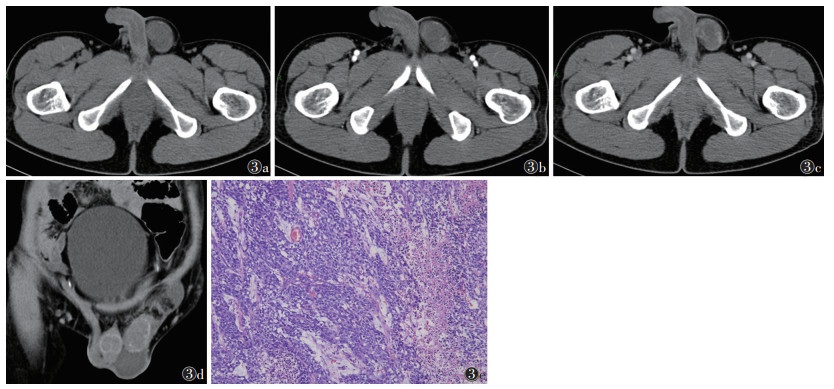

4例中,1例位于右侧睾丸,3例左侧。睾丸密度不均,CT值20~50 HU,中心见液化坏死区,肿瘤实性成分呈轻中度强化,强化较均匀,囊性坏死区无强化,边界不清,周围脂肪间隙消失,肿块内未见脂肪及钙化成分(图 3)。

| 注:患者,男,33岁。图 3a~3c分别为平扫、动脉期和静脉期图像;平扫图像示睾丸体积轻度增大,见类圆形肿块,密度不均匀,形态较规则,中心见少许液化坏死区;动脉期肿瘤实性成分呈轻中度不均匀强化,未见钙化及脂肪成分;静脉期肿瘤强化程度减退。图 3d为冠状位重建图像,可见明显鞘膜积液。图 3e为病理图像,示肿瘤细胞排列成腺泡状、管状、乳头状或实性结构,伴合体性生长及坏死、出血和纤维化区域,细胞异形性显著,核大而突出,可见瘤巨细胞和奇异性肿瘤细胞,核染色质粗糙,核膜清楚,核仁明显,可见病理性核分裂象(HE染色,高倍放大) 图 3 睾丸胚胎性癌CT图像及病理图像 |

胚胎性癌为高度恶性肿瘤,多见于20~30岁,其主要特征是肿瘤短期迅速增大,以实性成分为主,常有广泛出血、坏死,可伴少许钙化,易出现淋巴结及血行转移,增强扫描不均匀强化[9-10]。本组4例病变实性成分轻中度均匀强化,腹部未见明显转移,可能处于发病早期阶段。